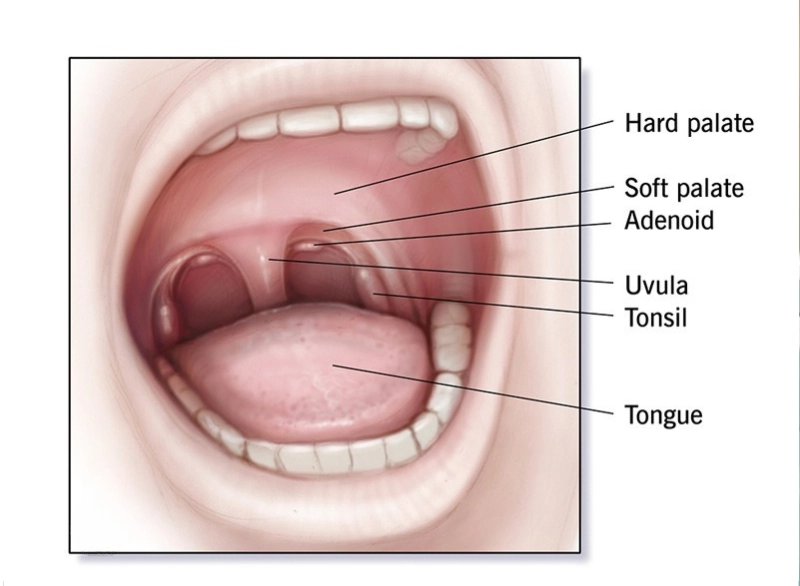

Adenoidectomy is the surgical removal of the adenoids—small lymphatic tissue located behind the nasal passage. When these become enlarged or infected frequently, they can block airways, cause snoring, breathing problems, and persistent ear or sinus infections.

Under general anesthesia, the adenoids are removed through the mouth—no cuts on the outside. The procedure takes less than an hour.